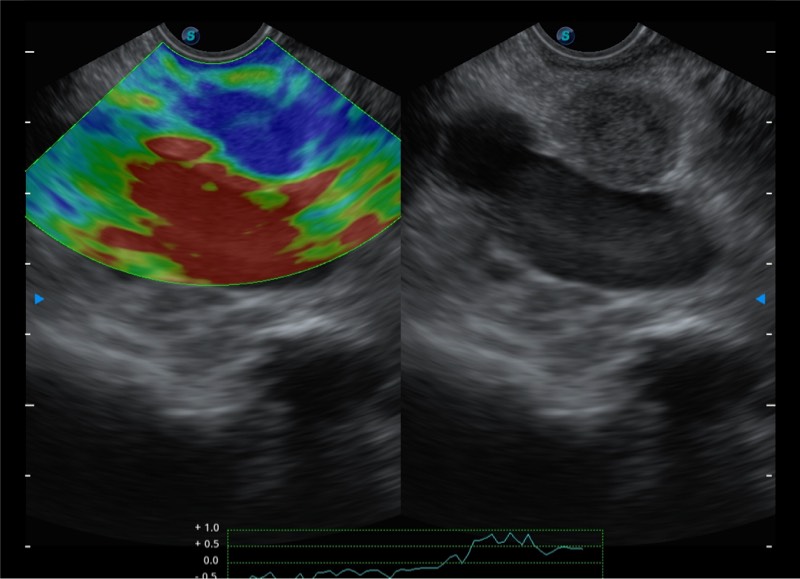

基于二十年的超声技术积累,乐玩lewin国际提供了最新一代的独立超声主机,在提供高质量图像的同时满足多学科使用。具备常见多普勒技术并提供弹性成像、声学造影等高端影像技术。新一代传感器具有更强的抗干扰能力并减少图像伪影。

4-12MHZ宽频输出

150°超声扫描角度